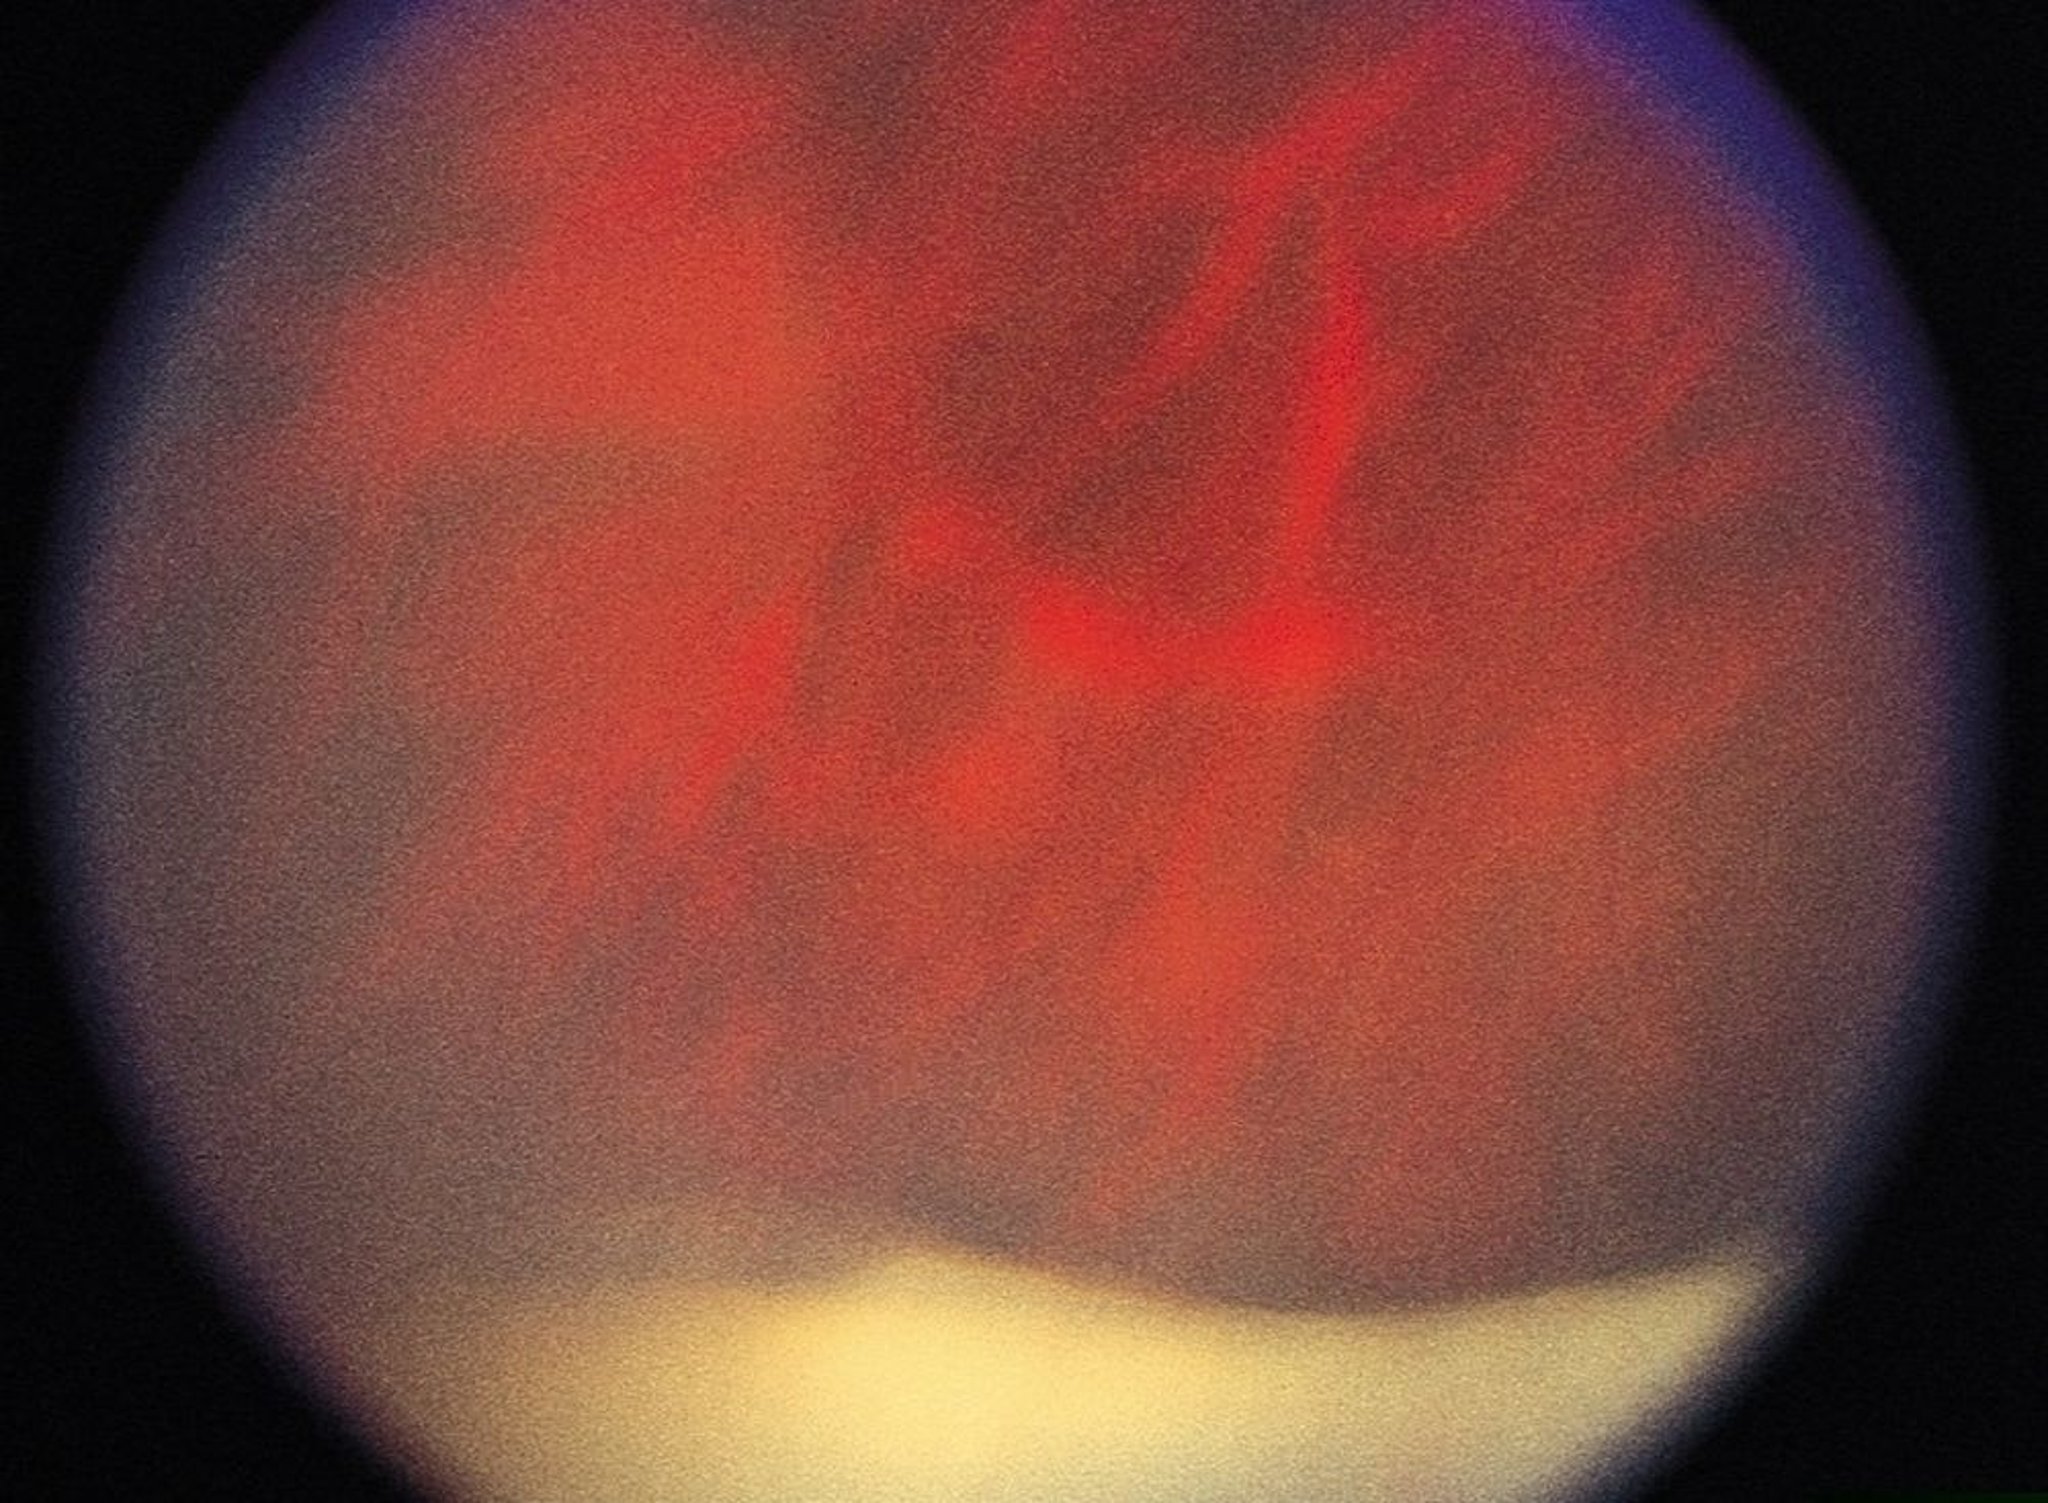

Uveítis (intermedia)

En la uveítis intermedia, los agregados de células inflamatorias pueden condensarse sobre la parte plana y parecer bolas de nieve; la confluencia de las llamadas bolas de nieve produce un aspecto clásico de "banco de nieve", visible (en esta imagen, la cubierta blanca en la parte inferior) con un oftalmoscopio indirecto.